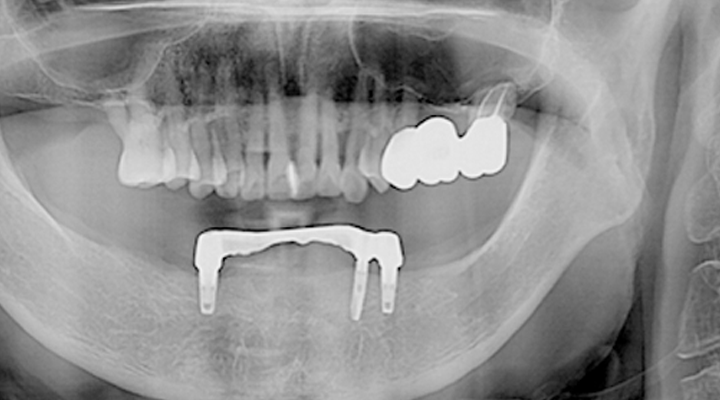

여러 개의 임플란트를 심은 뒤, 그 사이를 금속 막대로 연결해 튼튼한 지지대를

만들고, 그 위에 틀니를 안정적으로 고정하는 방식입니다.

적은 수의 임플란트를 심으면서도 입안의 틀니가 움직이지 않도록 고정해 주어 식사하는 데 부담이 적습니다.